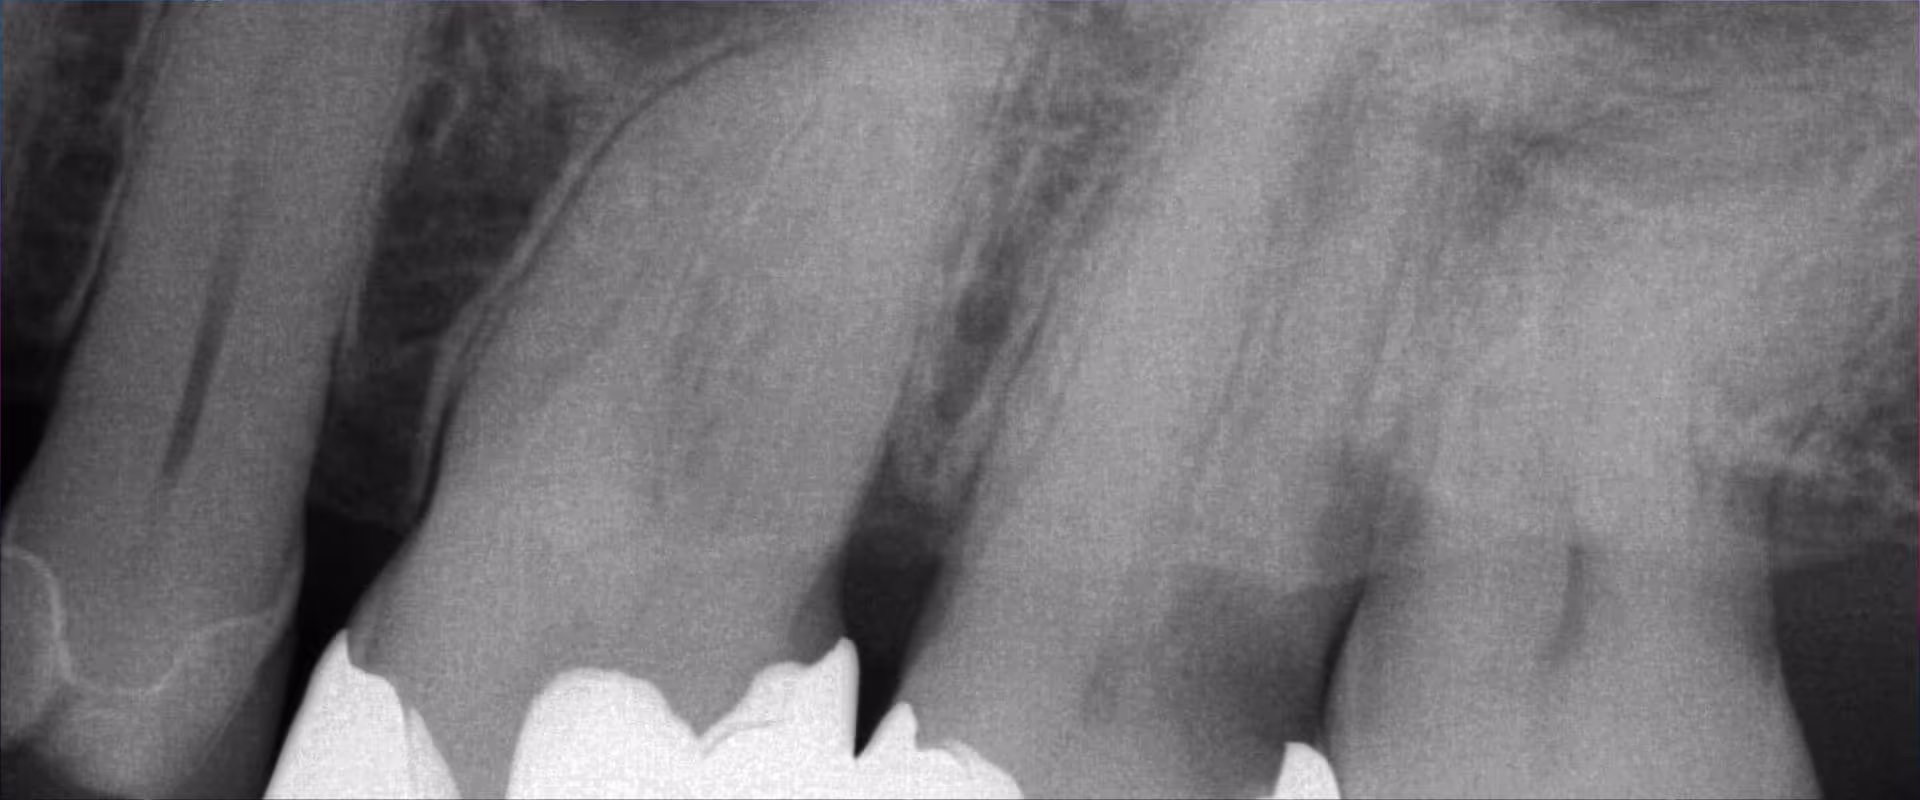

Viele Zähne, die endodontisch behandelt werden müssen, zeigen tiefe subgingivale Defekte. Der Vortrag zeigt Ihnen, wie Sie vor einer endodontischen Behandlung die Defekte sauber mit Komposit füllen können. Ich vermittle Ihnen Techniken zum Management von Blutungen, zum sauberen Anlegen von Matritzen, der Schaffung suffizienter Approximalkontakte und helfe Ihnen bei der Auswahl der optimalen Schichttechnik.